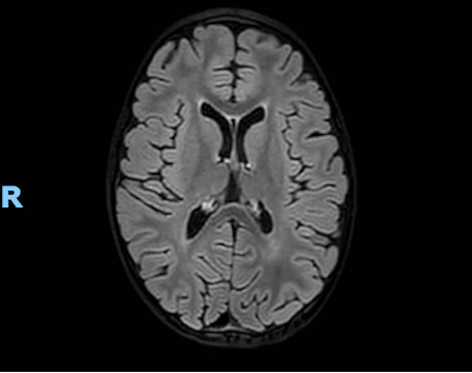

Per il quadro neurologico si richiede RM che evidenzia quadro di leucoencefalopatia con ipotrofia cerebrale (Figura 2). Dallapprofondimento anamnestico emerge che la bambina segue una dieta vegana e non ha mai eseguito integrazione vitaminica, dato confermato dal sopraggiunto valore di vitamina B12 (100 pg/ml, VN 191-663 pg/ml).